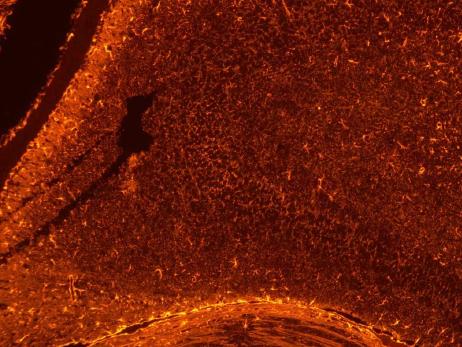

正置八孔LED熒光附件FL8-BGU-MH采用單色光譜范圍小的冷光源,最多可同時(shí)安裝8個(gè)不同波段大功率LED光源,完美取代汞燈光源,滿足對(duì)各種染料的觀察需求。

基于安全和操作便捷性的考慮,通過(guò)外置電源箱進(jìn)行驅(qū)動(dòng)。通過(guò)撥動(dòng)轉(zhuǎn)盤即可在明場(chǎng)或熒光的觀察方式之間進(jìn)行切換,方便快捷,提高工作效率,有效減少染料淬滅。

具有光強(qiáng)記憶功能,每個(gè)通道的亮度可以獨(dú)立控制。

支持用戶自己快捷拆卸和安裝熒光通道,安裝后無(wú)需調(diào)節(jié)即可使用。

15W大功率LED光源,使用壽命長(zhǎng),人工維護(hù)成本低。3.5英寸觸控液晶屏控制通道和亮度調(diào)節(jié)。

兼容蔡司、奧林巴斯、徠卡、尼康、耐可視、麥克奧迪等品牌顯微鏡的無(wú)限遠(yuǎn)光學(xué)系統(tǒng),支持通過(guò)熒光模塊升級(jí)實(shí)現(xiàn)熒光成像功能。